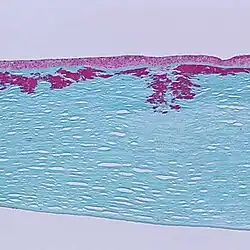

Reis-Bücklers corneal dystrophy is a disease of the eye, a rare corneal dystrophy of unknown cause, in which the Bowman's layer of the cornea undergoes disintegration. The disorder is inherited in an autosomal dominant fashion, and is associated with mutations in the gene TGFB1.

Patients with Reis-Bücklers dystrophy develop a reticular pattern of cloudiness in the cornea. This cloudiness, or opacity, usually appears in both eyes (bilaterally) in the upper cornea by 4 or 5 years of age. The opacity elevates the corneal epithelium, eventually leading to corneal erosions that prompt attacks of ocular hyperemia, pain, and photophobia. These recurrent painful corneal epithelial erosions often begin as early as 1 year of age.[1]

With time, the corneal changes progress into opacities in Bowman's layer, which gradually becomes more irregular and more dense.[1] Significant vision loss may occur.[2] However, vascularization of the cornea is not present.[2]